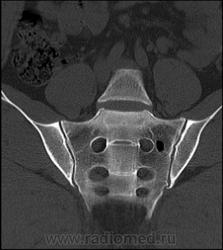

Случай 2: Внутрикостная пневмоцистика

Внутрикостная пневмоцистика